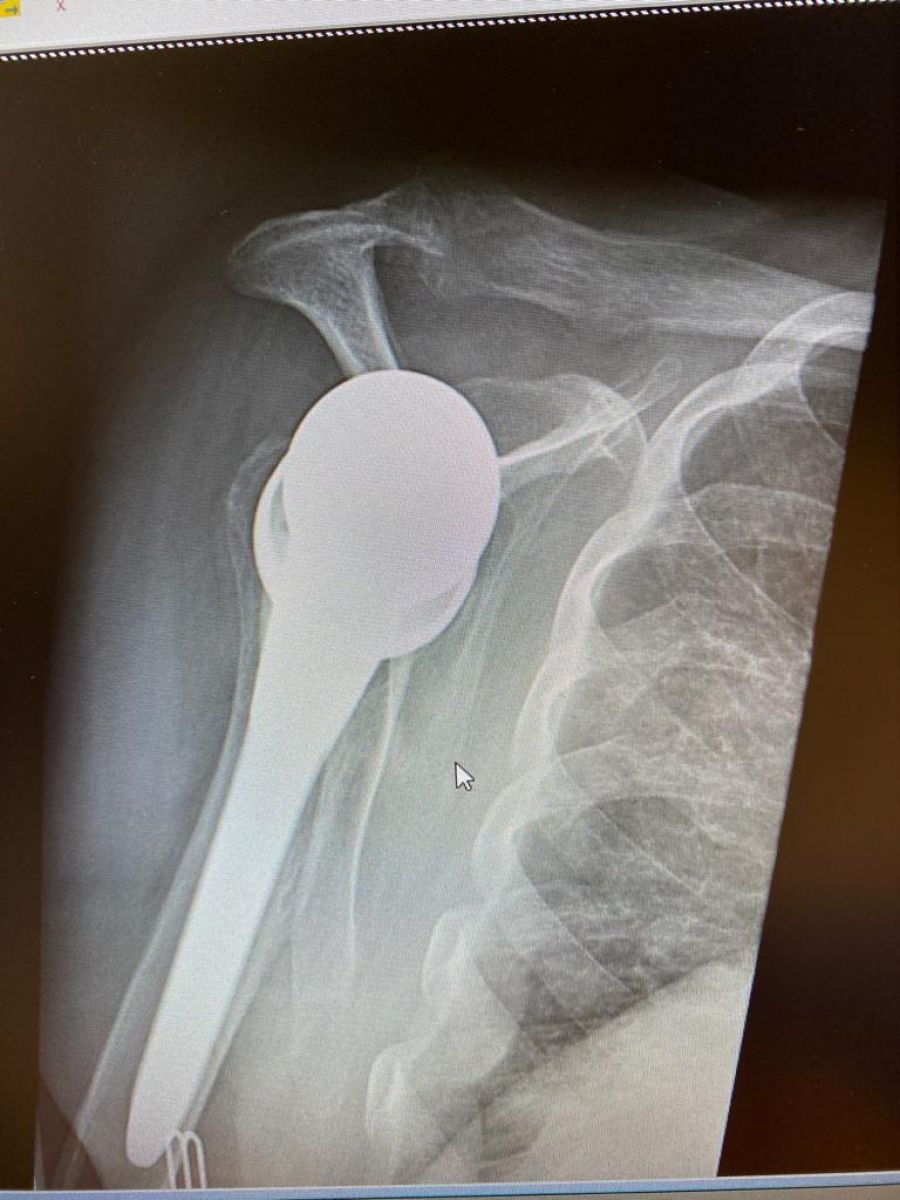

S-a specializat în chirurgia membrelor superioare la Centre Hospitalier Universitaire de Strasbourg, unde a aprofundat chirurgia specifică a cotului și umărului.

Dotați cu două camere amplasate pe rame, ochelarii HoloLens permit atât filmarea unui pacient în timp real, cât și reproducerea scheletului folosind o hologramă, totul de la distanță. Această proiecție tridimensională se potrivește direct în câmpul vizual al utilizatorului. Iar botoșăneanul Jean Ciornohac a efectuat deja două operații de succes cu dispozitivul inovator, astfel ajungând să reprezinte Belgia la amintitul eveniment.

”Astăzi avem posibilitatea de a reuni virtualul cu lumea operațională. Scopul operației este de a putea standardiza procedurile chirurgicale. Setul cu cască îmi permite, de asemenea, să explic pacientului operația mea și să reduc erorile medicale, erorile umane Este minunat să aducem această tehnologie în sala de operație și să putem reconstrui o articulație care este distrusă”,